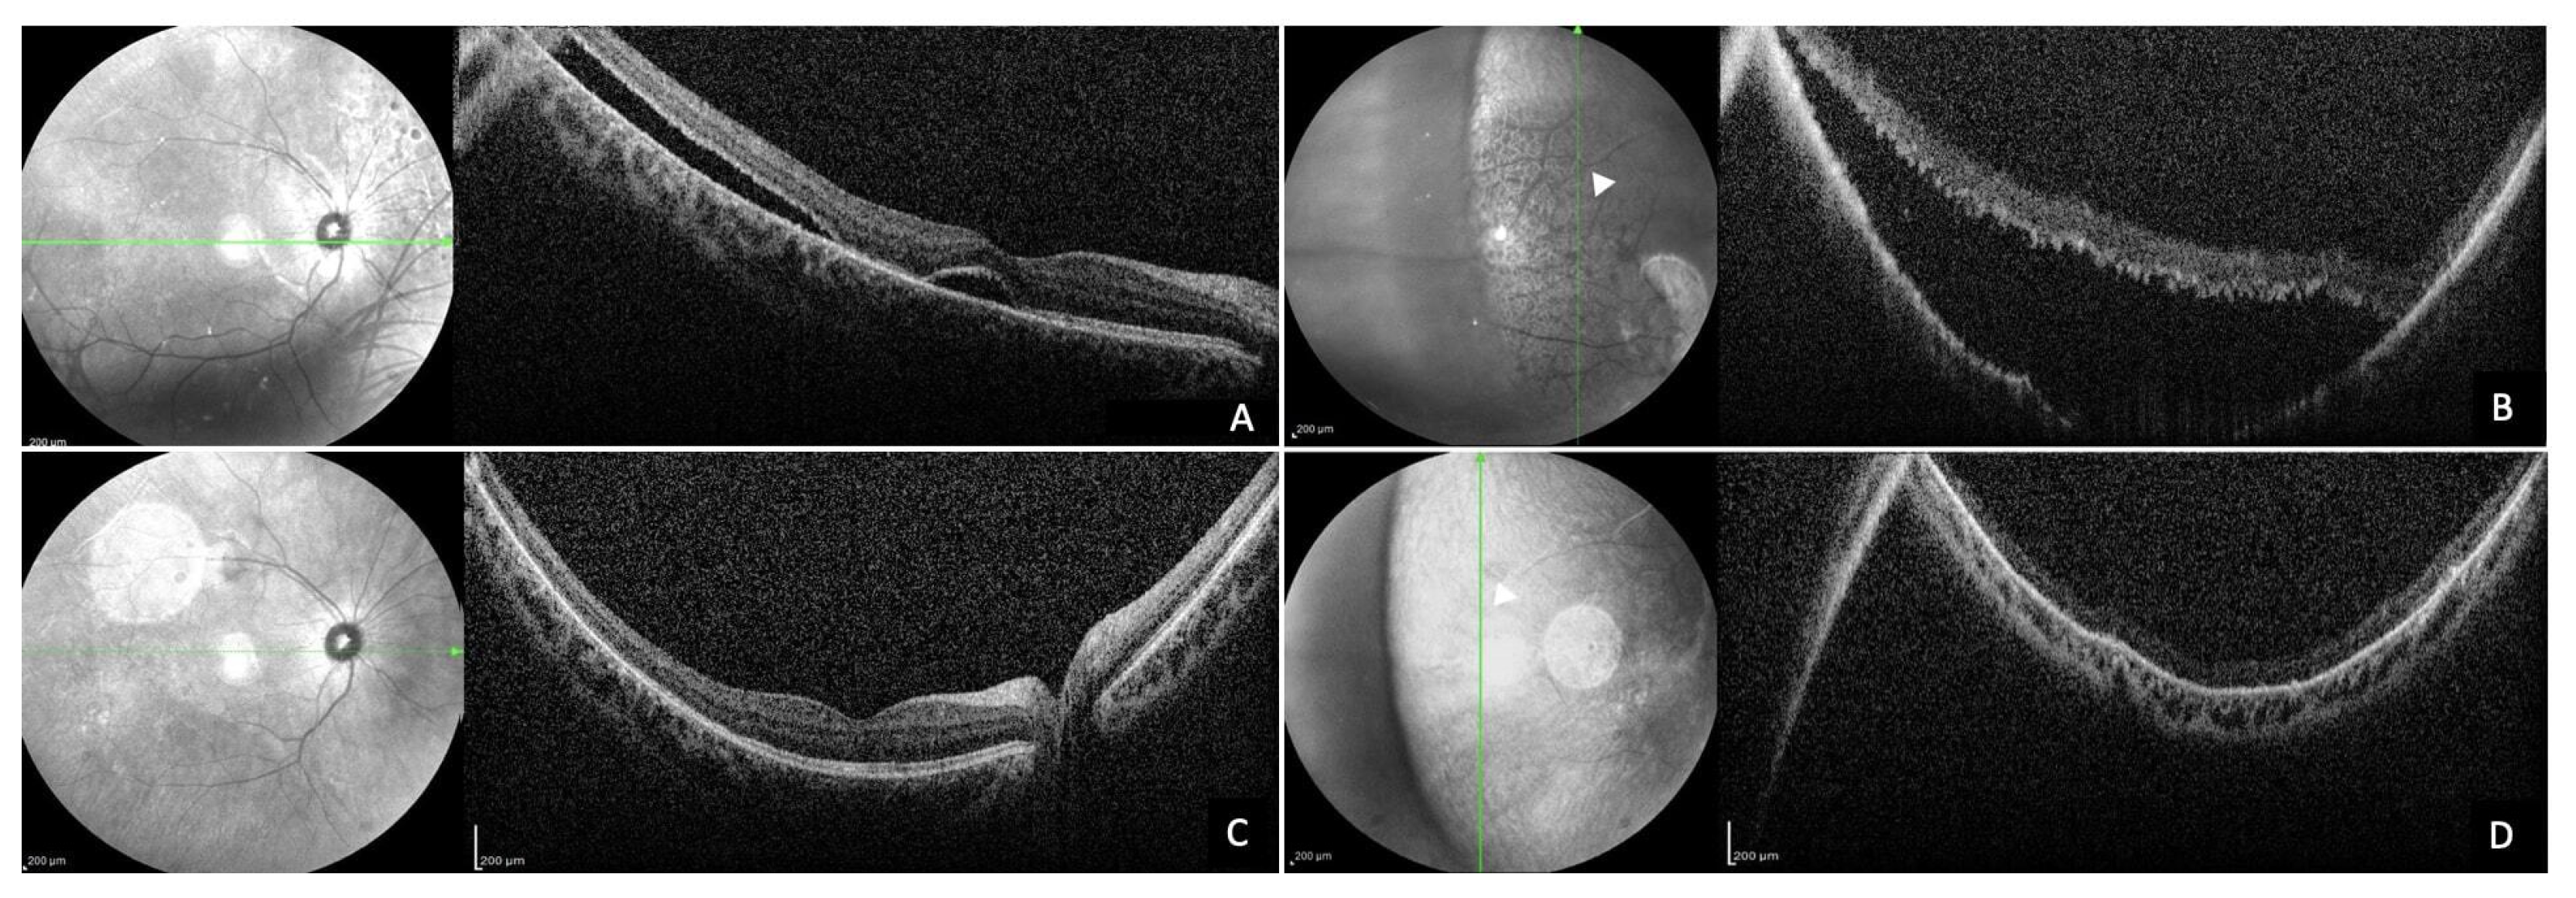

2.4. Optical Coherence Tomography Assessment